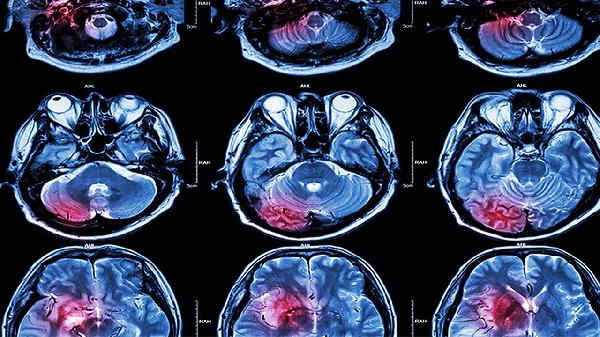

3.MRI脑梗死发病几小时后即可显示T1低信号,T2高信号病变区。CT相比,MRI可发现脑于、小脑梗死和小灶梗死。